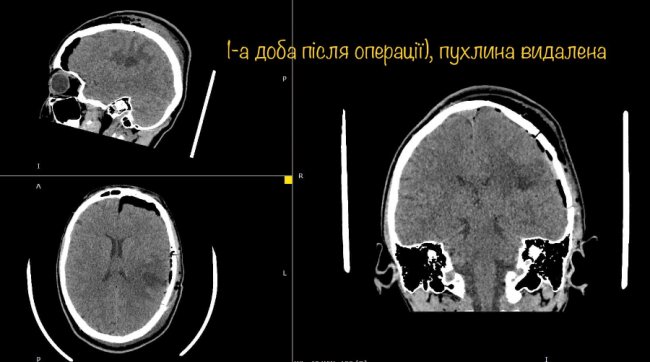

Діана вже через годину після операції вільно розмовляє, звичайно рухає усіма кінцівками і ні на що не скаржиться.